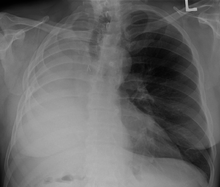

A chest x-ray of a person who has had their right lung removed

The most common reason for a pneumonectomy is to remove tumourous tissue arising from lung cancer. In the days prior to the use of antibiotics in tuberculosis treatment, tuberculosis was sometimes treated surgically by pneumonectomy.